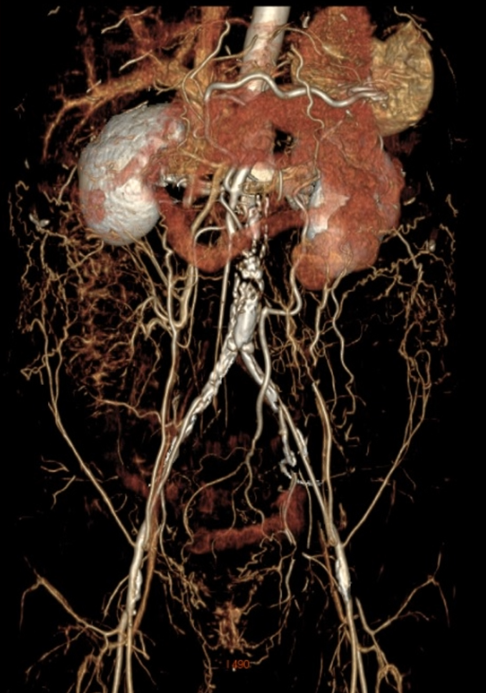

CTA:主髂动脉完全闭塞,钙化严重。

CTA